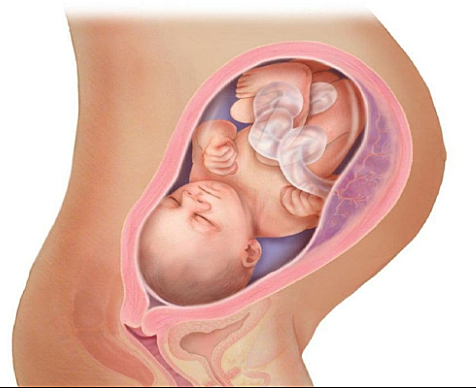

El bebé mide aproximadamente 46 centímetros y pesa alrededor de 2,200 gramos. Sus pulmones ya están casi completamente formados y sus huesos se han ido endureciendo pero todavía son muy flexibles, incluidos los de la cabeza.Su cráneo todavía no está completamente cerrado, lo cual le permite adaptarse con mayor facilidad al canal de parto en el momento de nacer. Por eso, algunos bebé nacen con la cabeza en forma de cono o aplastada, pero esto se revierte a los pocos días de nacer.

• Semana 35

Semana 35

Los pulmones del bebé acaban su proceso de maduración. Pero se debe estar pendiente de signos de parto prematuro (contracciones , sangrado vaginal o rotura prematura de membranas) porque todavía es pronto para dar a luz. Notarás mucha presión del bebé en la pelvis y la vulva e incluso calambres en la vagina. El bebé pesa unos 2.500 gramos y mide alrededor de 45 centímetros en la semana 35 de embarazo. A partir de ahora, los pulmones del bebe ya están maduros.